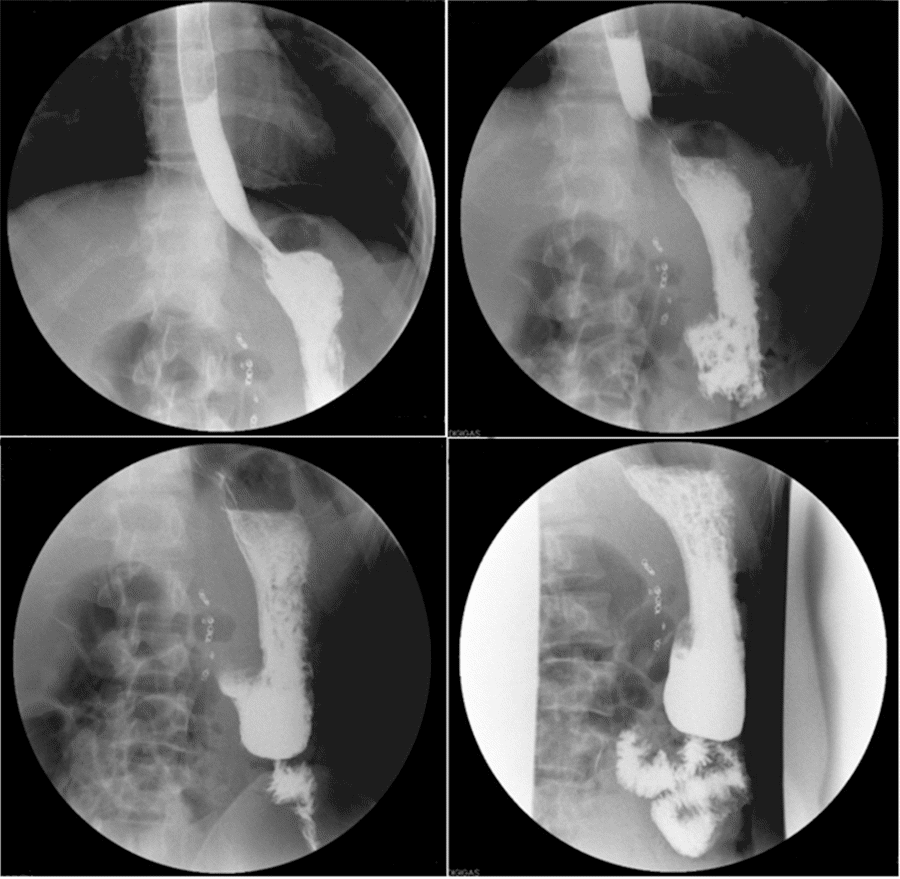

On postoperative day 1, the patient was noted to be feeling well with no acute overnight events. That morning, an upper gastrointestinal series (UGI) with water-soluble iodinated contrast revealed a normally distended stomach and normal transit of contrast into the proximal jejunum without evidence of obstruction or extraluminal extravasation (Figure 9).

Figure 9. XR Upper from GI Series POD 1. Published with Permission

Water-soluble iodinated contrast shows normal contrast transit into proximal jejunum without evidence of obstruction or extraluminal extravasation. Images taken within two-minute period.

The patient was then discharged home on postoperative day 1 on a full liquid diet for five days and was directed to advance to a regular diet as tolerated. He followed the instructions and denied nausea, abdominal pain, or distention with diet advancement. During the postoperative outpatient visit on day 22, his BMI was 18.6 kg/m2. He reported near immediate and complete resolution of symptoms with significant improvement in his quality of life. At the four-month postoperative visit, he reported feeling well, eating a regular diet, and having satisfactory weight gain.